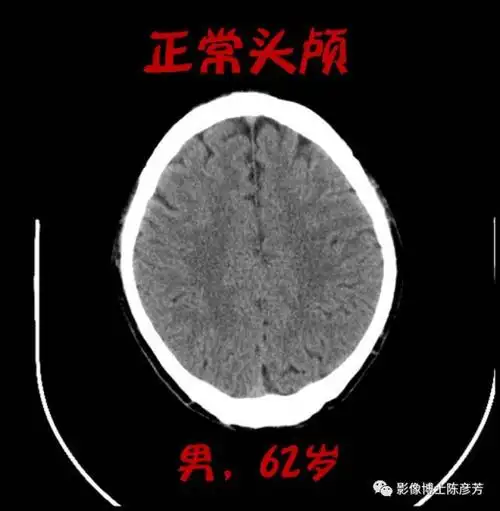

医学x光片脚掌骨骼